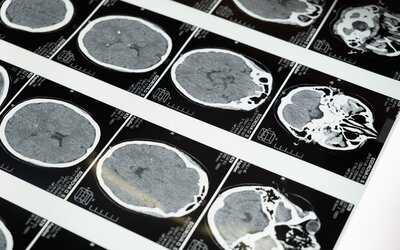

Al año en España cerca de 50.000 personas nuevas se sienten “congeladas” por las secuelas físicas del ictus. Aproximadamente 120.000 personas sufren un ictus en España cada año. Tras un ictus, el 40% de quienes lo padece tendrá como secuela algún grado de espasticidad...